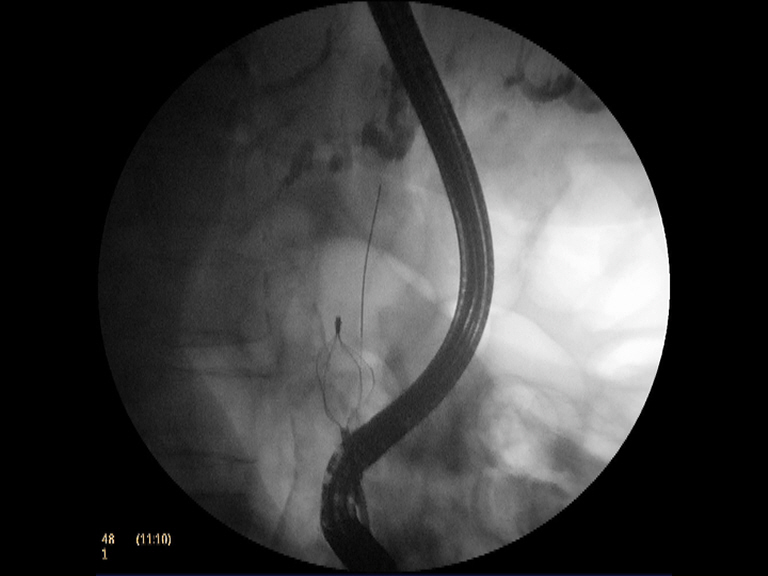

Paciente mujer de 82 años de edad con antecedentes de DM tipo II en tratamiento con insulina y síndrome de bradi-taquiarrtimia (portadora de marcapasos). Ingresa en el hospital por una fractura de cadera que se interviene quirurgicamente. Tras la intervención se practica un control analítico donde se aprecia una elevación de la GGT (519 UI/l) asintomática. La ecografía subsiguiente refleja una importante dilatación de la vía biliar (intra y extrahepática), con un colédoco de 22 mm, en cuyo interior se observa una coledocolitiasis de gran tamaño (22 mm), así como una colelitiasis en el contexto de una vesícula escleroatrófica. Se decide realizar CPRE para extracción de la coledocolitiasis. la canulación es sencilla, observando en la colangiografía una marcada dilatación de la vía biliar extrahepática (> 20 mm) con varias coledocolitiasis, dos de ellas de gran tamaño (unos 22 mm). Destaca el afilamiento distal del colédoco y la morfología cuboidea asimétrica de las litiasis de mayor tamaño. Con estos tres datos: gran tamaño de la CD, afilamiento distal del colédoco y morfología de las litiasis (cuboideas con eje mayor no alineado al colédoco), la extracción estándar con papilotomía y uso de balones o cestas parecía inviable. Había que usar una técnica alternativa (esfinteroplastia con balón CRE de gran tamaño, superando los 18 mm) quizás combinada con la litotricia mecánica. De forma sistemática, esto fue lo que hicimos con éxito.

La coledodolitiasis continúa siendo la indicación mas común en la CPRE. En muchos casos sigue siendo un reto para el endoscopista biliar, especialmente si son de gran tamaño, morfología asimétrica, de composición dura y el colédoco distal está afilado. En estos casos, hasta hace unos 6-7 años, se usaba exclusivamente la litotricia mecánica, la cirugía o en pacientes añosos y plurupatológicos, el empleo permamente (con recambios periódicos) de prótesis plásticas. Ultimamente se está realizando la esfienteroplastia del esfinter biliar con balones CRE de gran tamaño (hasta 20 mm), según el calibre del colédoco y el tamaño de la vía biliar (técnica DASE). No obstante, aún así, en muchos casos es imposible su extracción incluso con la dilatación y hay que complementarla con la litotricia mecánica (EML) alcanzando una tasa de éxitos del 95 %. En el otro 5 % de los casos muy rebeldes hay que usar técnicas como la litotricia electrohidraúlica (EHL) o por láser (LL) mediante colangioscopia o gastroscopios ultrafinos.